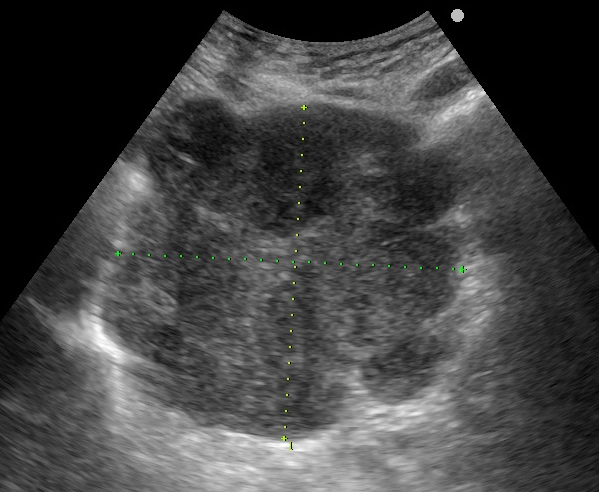

66歲女性,每年定期做健檢,今年預計四月中旬做健檢,四月初就開始感覺腸胃不適,但礙於新冠疫情,她想拖到健檢時再一併解決,沒想到健檢當天被退貨,醫師摸摸她的肚子,評估她必須先去看門診。

KUB看不出她的病有多嚴重: